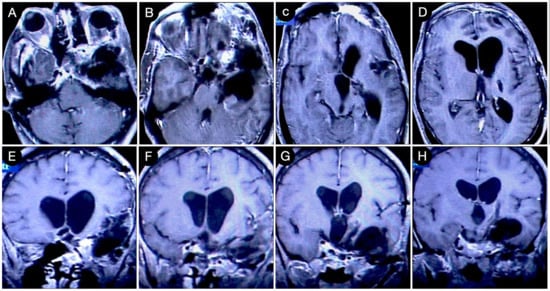

Case #8: Aggressive ACTH Tumor with Multiple Recurrences